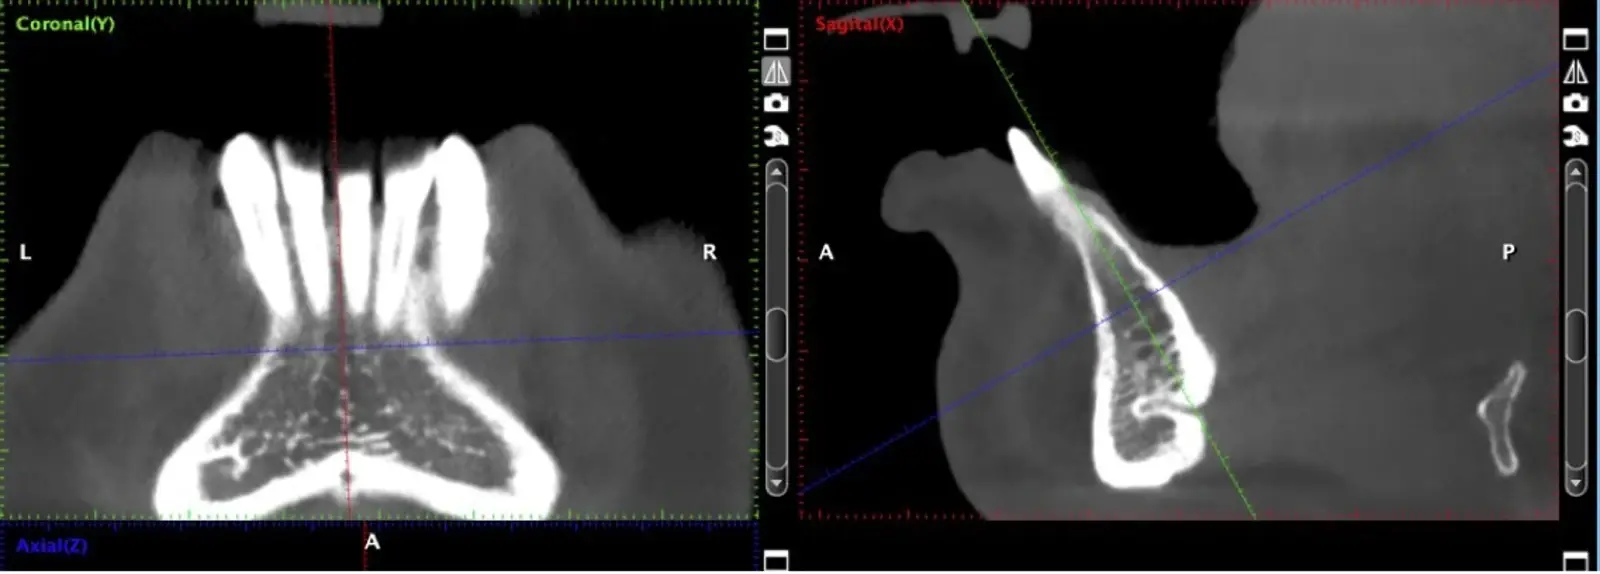

El hueso autógeno, considerado como el “gold stándard” para la regeneración ósea, no produce reacciones inmunológicas y contiene componentes osteogénicos, osteoinductores y osteoconductores.7,8 Suele obtenerse en bloques y las zonas dadoras intraorales de elección son la sínfisis mentoniana y la rama mandibular.9

La literatura menciona varias complicaciones relacionadas con la extracción de injertos óseos, la mayoría de ellas asociadas con el corte y la manipulación de zonas próximas a estructuras de riesgo; entre las más comunes, las lesiones nerviosas con consecuente adormecimiento, molestias postoperatorias (abertura bucal limitada, sangrado, hinchazón y dolor) y problemas estéticos (cambios en el contorno del área donadora o recesión de tejidos blandos).10 Aunque los injertos de rama pueden presentar menos molestias postoperatorias, tienen un acceso quirúrgico limitado debido a la apertura bucal y el peligro potencial de lesionar el paquete vásculo-nervioso cercano.11

La osteotomía con insertos de piezoeléctrico nos permite un corte más definido con menor pérdida de hueso residual, ya que los insertos son extremadamente finos.